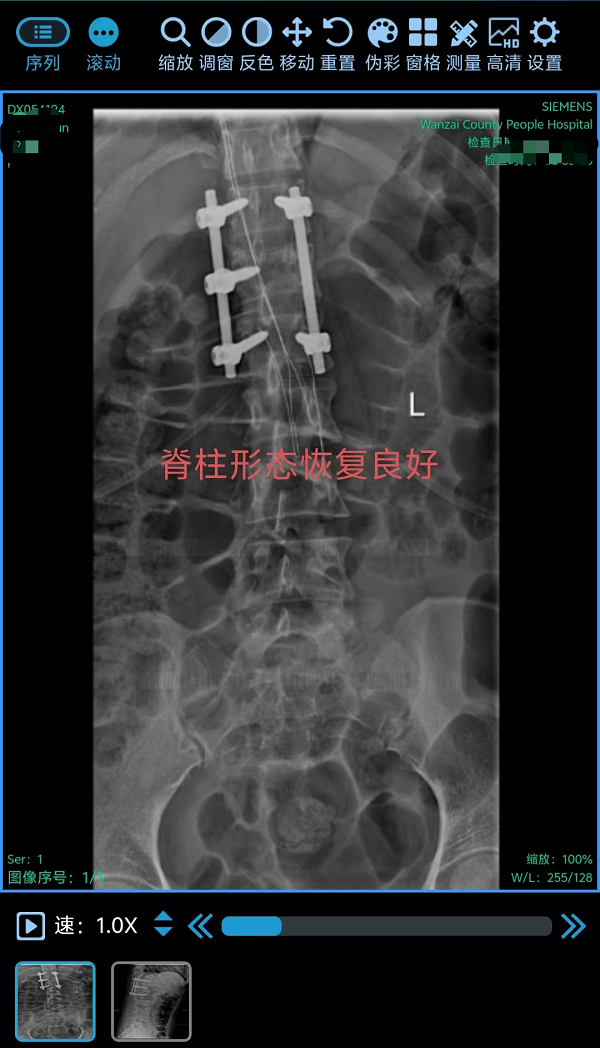

3. 为胸椎爆裂性骨折患者施后路切开复位、微创减压内固定术(四级手术),胸椎爆裂性骨折常因高能量损伤导致,骨折块可能突入椎管压迫脊髓,致残风险高。丁晔副主任医师团队采用微创理念进行减压,并完成了有效的复位与坚强的内固定,既解除了对神经的压迫,又最大程度地减少了手术创伤,为患者争取了最佳的神经功能恢复条件。

三台手术均顺利完成,患者术后恢复良好,标志着我院脊柱疾病微创化、精准化治疗迈上新台阶。